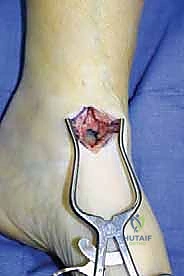

هو إحداث توازن مثالي بين الجراحة المفتوحة وجراحة المناظير. يقوم الأستاذ الدكتور محمد هطيف بإجراء الجراحة عبر شقين أو ثلاثة شقوق صغيرة جداً (لا تتجاوز 2-4 سم). من خلال هذه النوافذ الصغيرة، وباستخدام أدوات جراحية دقيقة ومخصصة، يتمكن من الرؤية المباشرة للمفصل، وإزالة الغضاريف التالفة بالكامل، وتجهيز العظام للدمج، ثم تثبيتها بالبراغي.